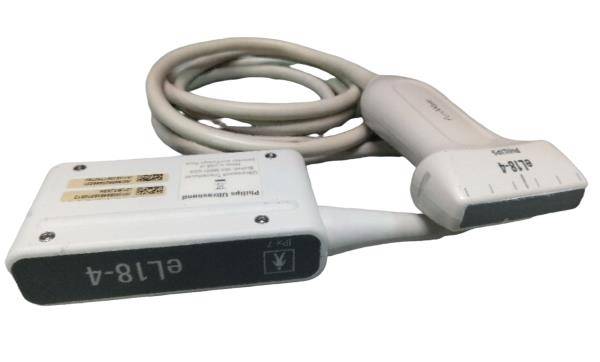

Versatile Probes for Different Needs

Equipped with the S3-1 and L9-3 transducer probes, the Philips IU22 offers versatility that caters to diverse clinical needs. The S3-1 probe is excellent for abdominal and obstetric examinations, while the L9-3 probe specializes in cardiac imaging. Additionally, these probes are designed for user comfort, reducing the strain during prolonged procedures. Thus, healthcare professionals can provide more efficient and comfortable patient care.